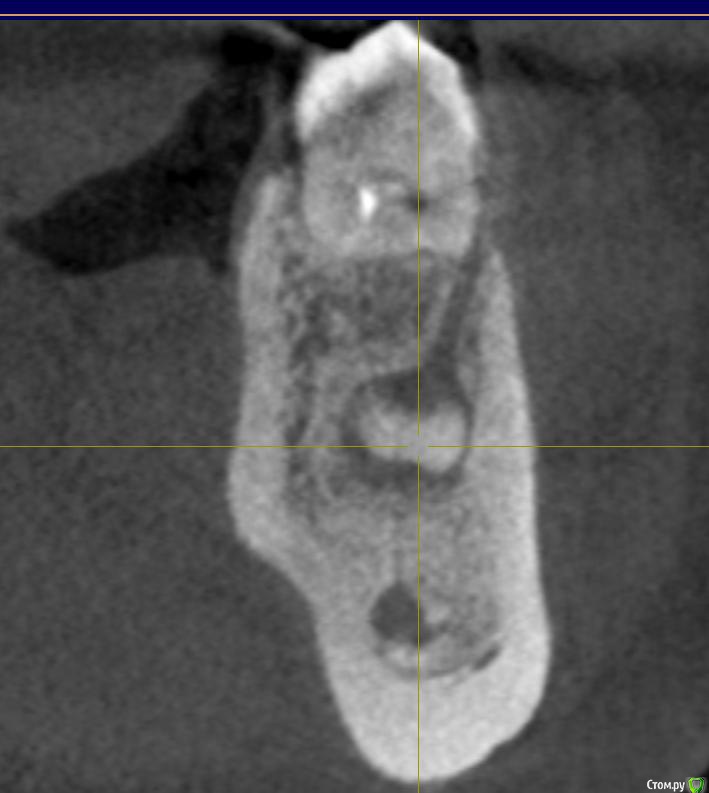

Ксения_ Опубликовано 27 августа, 2015 Поделиться Опубликовано 27 августа, 2015 (изменено) Здравствуйте Уважаемые Доктора! КТ сделано 4 мес назад. После этого пролечен кариес 14, 16, 37, 35. Пролечен пульпит 25, 36.Осталось пролечить пульпит в 15, 26, 47. Удалить все восьмерки.Далее ортодонтия. Стоит вопрос об удалении 46. Зуб ранее был пролечен другим врачом некачественно (+ пропущен канал).Мой лечащий доктор, после консультаций с коллегами, предлагает удаление, т.к. с его слов прогноз у этого зуба неблагоприятный (считает, что через пару лет процесс повторится) и смысла в столь дорогом лечении нет. Мне, конечно, хотелось бы по возможности зуб сохранить.Как вы считаете какой прогноз у этого зуба? P.S. Зуб не беспокоит. Точнее ни один зуб у меня вообще ни разу в жизни не болел (несмотря на такое количество пульпитов, которые для меня были неожиданностью. Врачу своему доверяю.). Несколько докторов которые меня смотрели считают, что у меня высокий болевой порог. Изменено 27 августа, 2015 пользователем Ксения_ Ссылка на комментарий

M@estro Опубликовано 27 августа, 2015 Поделиться Опубликовано 27 августа, 2015 (изменено) Судя по рентгену - прогноз благоприятный. Зуб сохранен,это главное. "процесс повторится" - на это при современном подходе выделяют не более 5 % .Если бы у меня 95 % вероятности в казино было - я бы дом поставил , не то что зуб полечил ) Ключевое при перелечивании - соблюдение современного протокола лечения. P.s. После лечения уже больше двух лет прошло,недавно был на осмотре - процесс все никак не повторится )) Изменено 27 августа, 2015 пользователем M@estro 3 Ссылка на комментарий